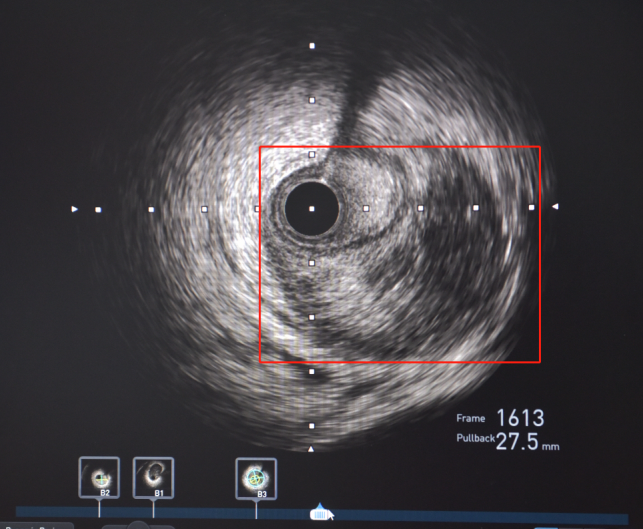

随后,患者立即被送往导管室,揭主任携副主任医师蒋溢为迅速给患者完成了冠脉造影,术中见患者左主干明显变窄,回旋支闭塞,血流TIMI0级,前降支次全闭塞,血流TIMI1级。但此时尚未能明确患者是否为冠脉痉挛或冠脉自发夹层,揭英纯和蒋溢为副主任医师当机立断,为患者快速完成了血管内超声检查,原来是冠状动脉自发夹层!考虑到患者冠脉已经闭塞,遂在IVUS指导下选择切割球囊精准对闭塞血管进行切割扩张,恢复回旋支及前降支正常血流。

左主干至回旋支、前降支自发性冠状动脉夹层、血肿压迫真腔

血管再通,血流恢复正常